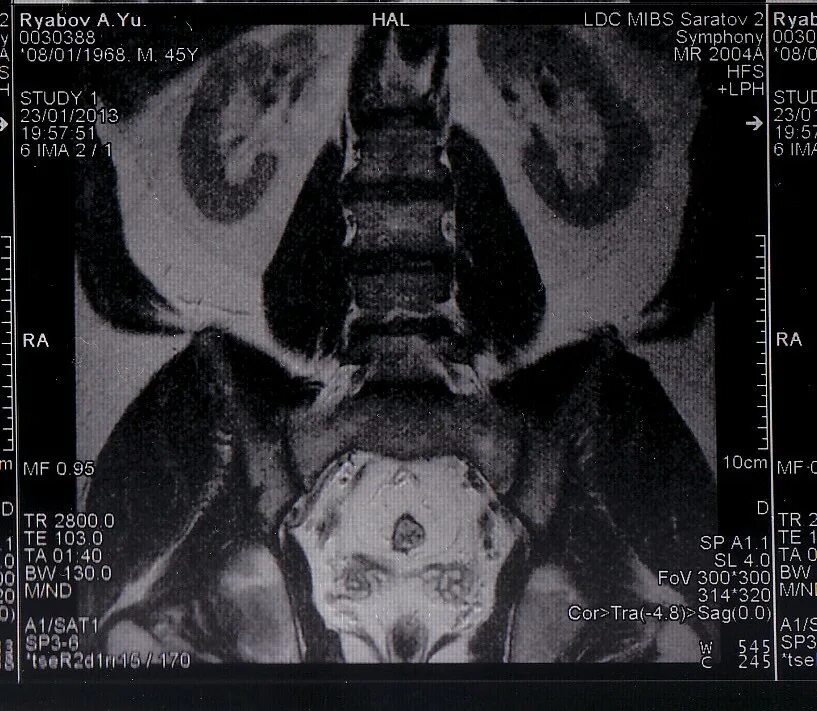

Сколько делается мрт пояснично крестцового отдела